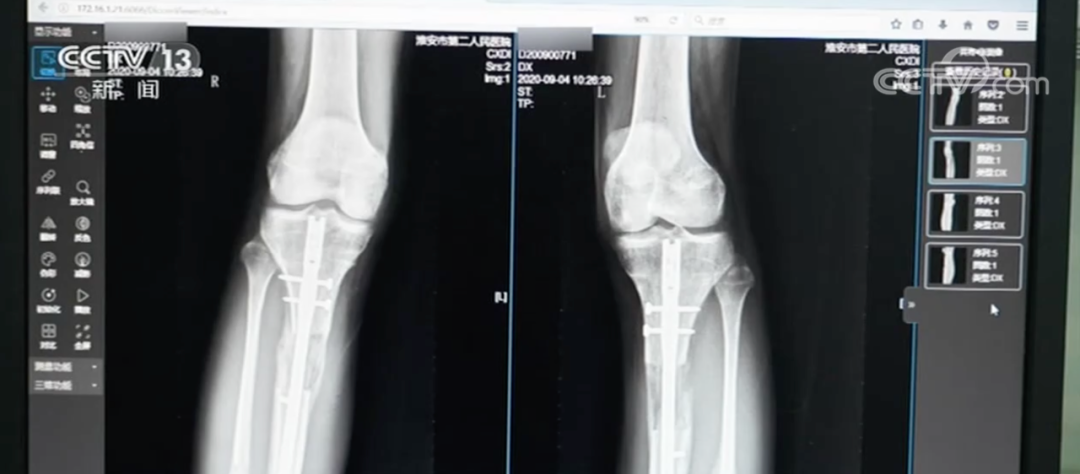

近日,江苏省淮安市第二人民医院接诊了一名特殊患者。这名患者因为对自己的身高不满,在国外做了“断骨增高手术”,结果导致双腿严重感染无法行走,甚至面临终身残疾。

此外,“断骨增高手术”还具有多方面的危害。王磊表示,在实施断骨增高手术时,外固定“增高器”的钢针要穿透患者的双腿,可能损伤腿部的血管、神经组织,造成感染,甚至引发骨髓炎,造成残疾。同时,断骨增高手术会造成血管损伤,严重的腿部血液供应障碍可能造成下肢组织坏死。